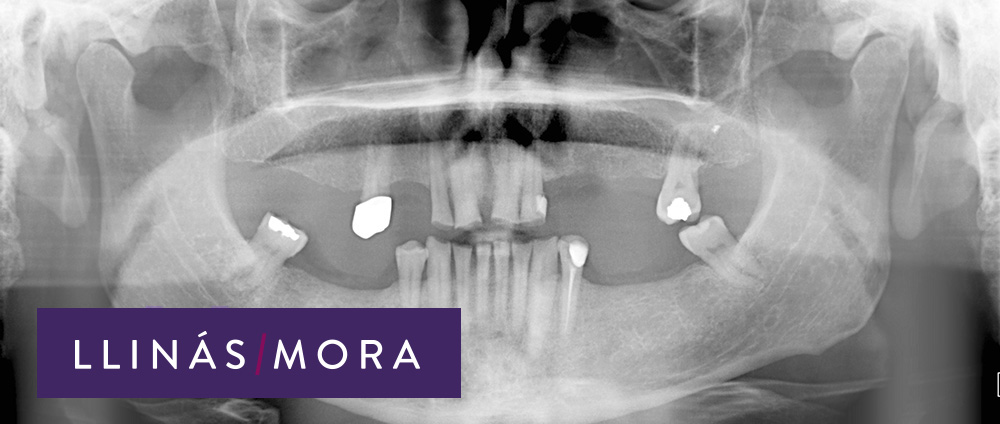

2. Ausencias dentales multiples y mordida descompensada con desgaste avanzado de los dientes. (Radiografía)